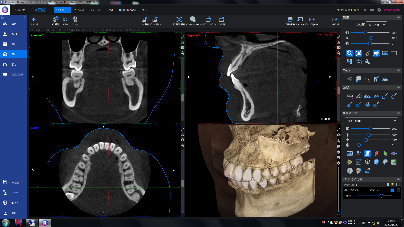

■3Dエックス線撮影(CBCT)

歯や骨の状態を3次元的に調べるエックス線検査で、通常のエックス線写真では重なりが生じて見えない病気の発見や、病変の大きさ、位置関係などを調べられる為、歯科医師がより正確な診断、治療をするのに役立ちます。

歯の欠損部位があり、インプラント治療をご検討されている方は、インプラント治療の可否を診断するうえで非常に重要な情報となります。